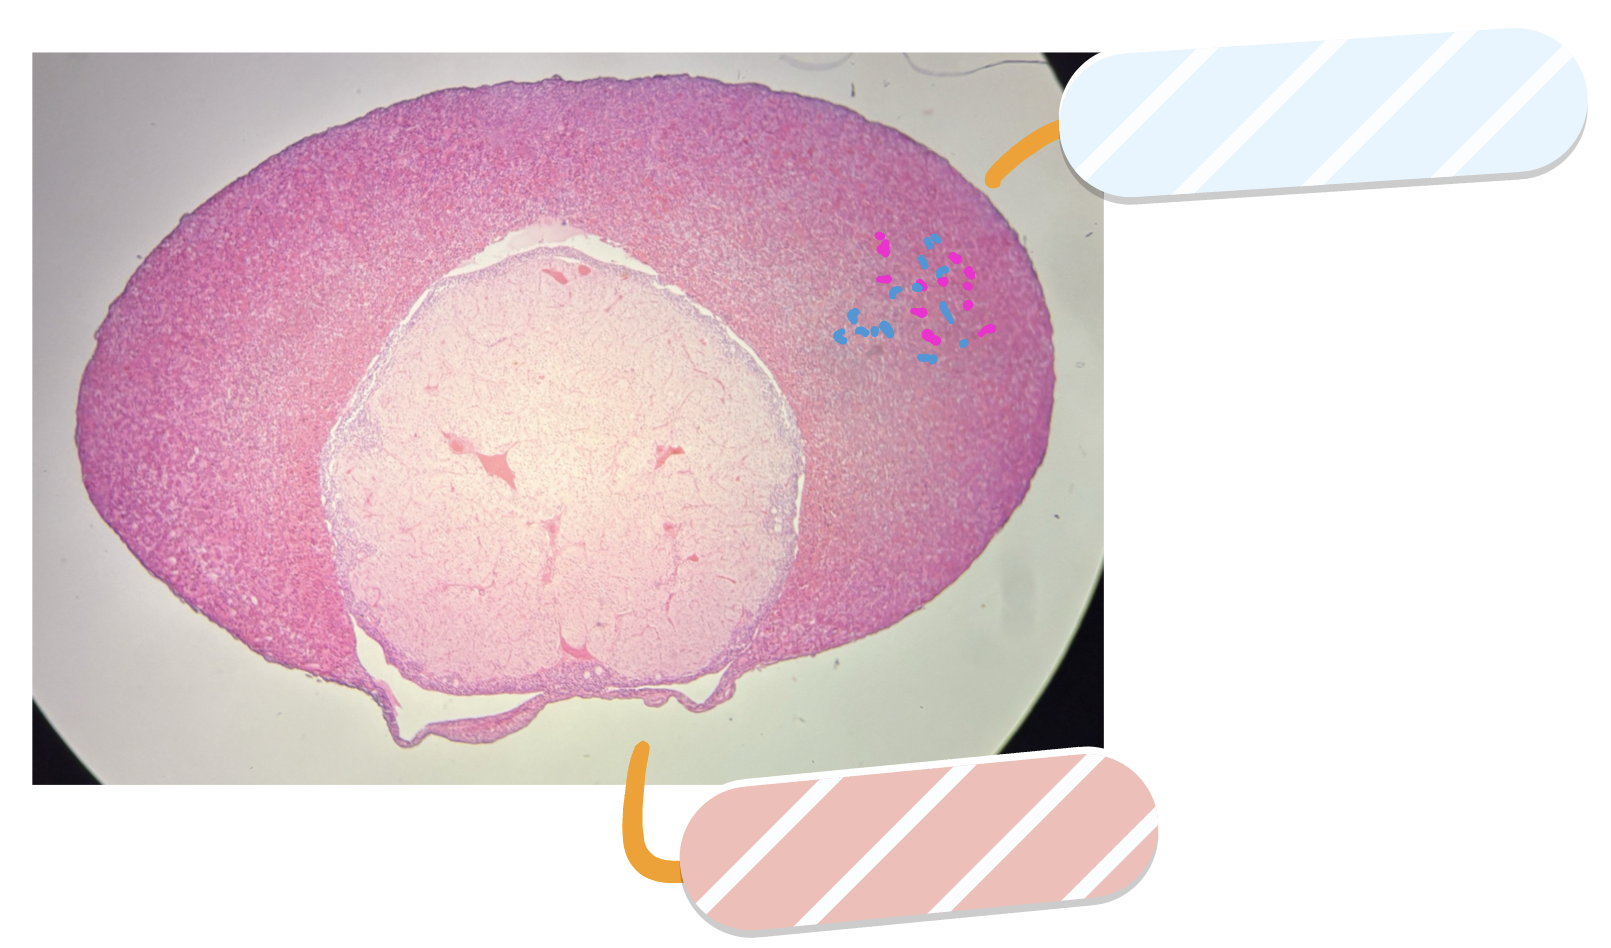

What is this a slide of?

Ovary

What is red?

Mature tertiary follicle

What is orange?

Primordial follicles

What is yellow?

Antrum

What is green?

Corona radiata

What is cyan?

Oocyte